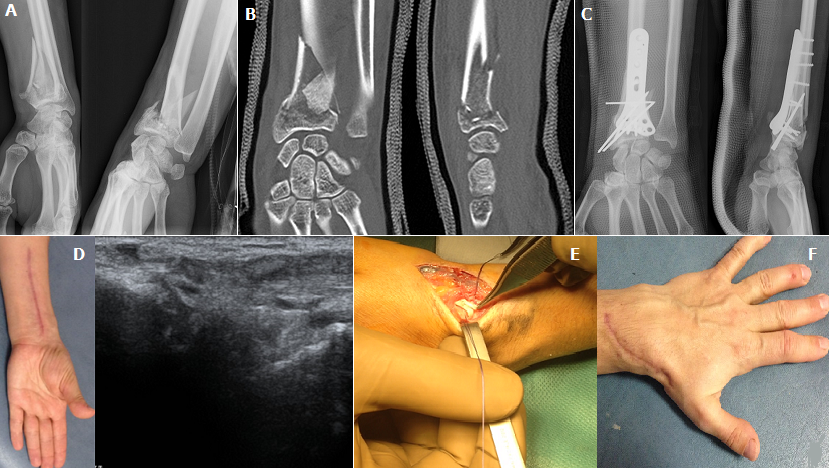

Nous rapportons le cas d'une patiente âgée de 36 ans, victime d'un accident de sport à l'occasion d'une chute d'un cheval. Le bilan radiologique objectivait une fracture communitive fermée de l'extrémité inférieure du radius gauche avec déplacement important (A et B). La prise en charge initiale a consisté en une ostéosynthèse à foyer ouvert avec plaque antérieure vissée et des broches (C) suivie d'une rééducation fonctionnelle. L'évolution a été marquée par la survenue d'une rupture secondaire du long extenseur objectivé cliniquement par un déficit d'extension du pouce et confirmé par une échographie dynamique (D); la patiente a été repris chirurgicalement avec à l'exploration un tendon effiloché coincé dans un important cal osseux (E), le traitement conservateur était impossible, la réparation a consisté en une résection greffe partielle à partir du long extenseur radial du carpe après son dissection par la même voie d'abord. Le résultat après rééducation était excellent (F) avec reprise progressive du travail à partir du 2ème mois.